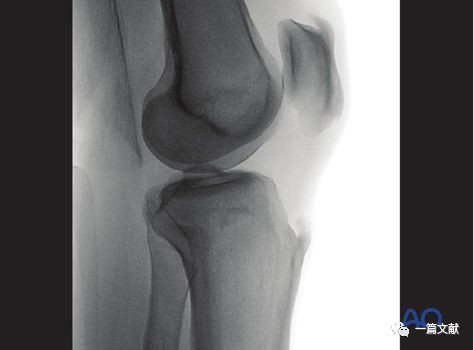

三,头倾10°的正位片

1)在标准正位的基础上,将C臂机向头端倾斜10°,抵消胫骨平台的后倾角,使射线完全平行于胫骨关节面。如下图:

2)头倾10° 正位的评估:1、胫骨平台关节线位于图像中央;2、内侧和外侧平台关节线分别显示位一根较粗的线。如下图:

3)解剖标志的识别:如下图:1、外侧平台关节面(凸面)2、内侧平台关节面(凹面)3、髁间脊4、闭合的骨骺线

4)头倾10° 正位片的意义:1、评估内侧和外侧平台复位情况;2、检视是否存在突入关节的内植物。